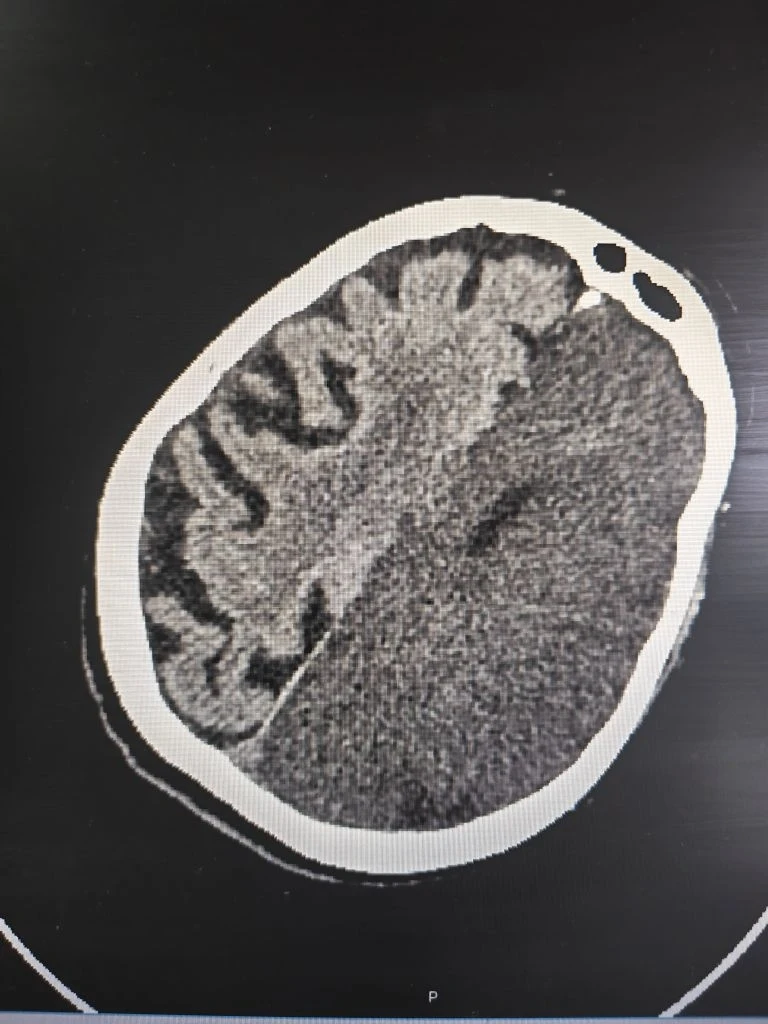

Срочно проведенная компьютерная томография подтвердила самые опасные опасения: у женщины диагностировали обширный ишемический инсульт. Это состояние означает, что из-за острого нарушения кровообращения значительный участок мозга перестал получать кислород, и клетки начали гибнуть. Подобный тип сосудистой катастрофы медики относят к числу наиболее тяжёлых: даже при своевременной помощи прогноз часто остаётся неблагоприятным, а риск летального исхода крайне высок.